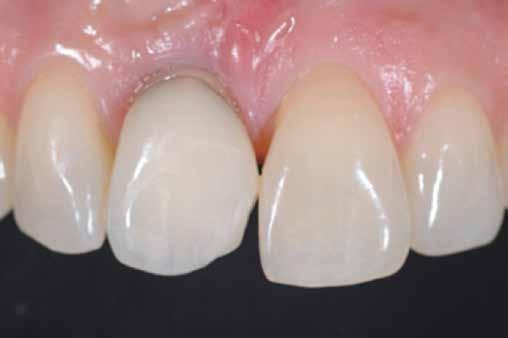

A betétek készítéséről készülök előadást tartani. Ez a terület hallgató korom óta tetszett, és mára a rendelőnkben végzett kezelések jelentős részét teszi ki.Héjkerámiák ragasztására váró fogak.

A cikkünkben bemutatásra kerülő eset ellátása során preparációt héjak készre vitele során a platinafólia technikát alkalmaztuk.

A fogászati kezelések során manapság már nem kizárólag az esztétikai megjelenés helyreállítására törekszünk. Sokszor a kedvezőtlen esztétikai megjelenés hátterében álló okok következményes módon a fogazat funkcionális működését is károsítják, így a kezelések során ezeknek a helyreállításával is foglalkoznunk kell. A különböző funkcionális és esztétikai diszkrepanciák kezelésére számtalan módszer létezik, ám ezen fogászati beavatkozások mindegyikében közös, hogy a kivitelezésük során nagyon szoros együttműködésre van szükség a kezelést végző fogorvos és a munkáját segítő fogtechnikus között. Az alábbi esetbemutatás során egy fiatal hölgypáciens fogazatának héjak alkalmazásával történő esztétikai és funkcionális rehabilitációját szeretnénk ismertetni.

A páciens fogazata esztétikai megjelenésének és funkcionális működésének a lehető legtöbb, saját foganyag megtartása mellett történő helyreállítása (1. és 3. ábra).